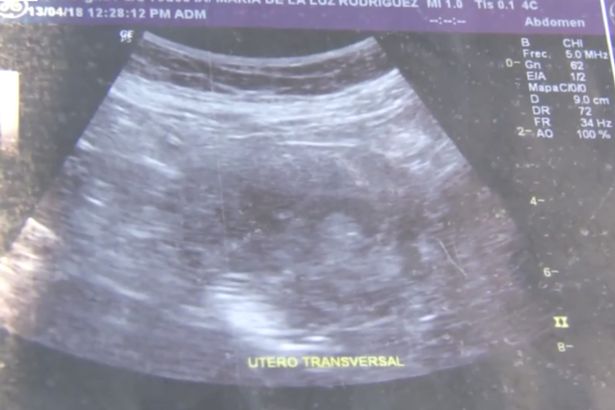

Mặc dù đã ở tuổi 70 nhưng bà Maria de la Luz, sống tại thành phố Mazatlan, bang Sinaloa, Mexico, vẫn đang mang thai đứa con thứ 8. Trên phương tiện truyền thông địa phương, bà Maria khẳng định mình đang mang thai ở tháng thứ 6 và hình ảnh siêu âm cho thấy đó là một bé gái.

“Tôi bị đau chân, thường xuyên cảm thấy buồn nôn và chóng mặt. Tính đến nay, tôi đã đi siêu âm 10 lần cả ở phòng khám tư nhân và bệnh viện an sinh xã hội. Các bác sĩ đều không thể tin được là tôi đang mang thai. Họ nói với tôi đó là một bé gái. Nhìn hình ảnh siêu âm, tôi có thể thấy khuôn mặt nhỏ bé của con gái mình“, bà Maria chia sẻ.

Hình ảnh siêu âm thai kỳ của bà Maria.